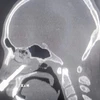

Ảnh minh họa

Bệnh nhân được chỉ định chụp CT não khẩn cấp cho thấy có xuất huyết dưới nhện lan tỏa hai bên - dấu hiệu điển hình của vỡ phình động mạch não.

Kết quả chụp phim dựng hình mạch máu não xác định người bệnh có hai túi phình, trong đó túi phình động mạch thông trước đã vỡ, túi phình còn lại ở não trước kích thước nhỏ.